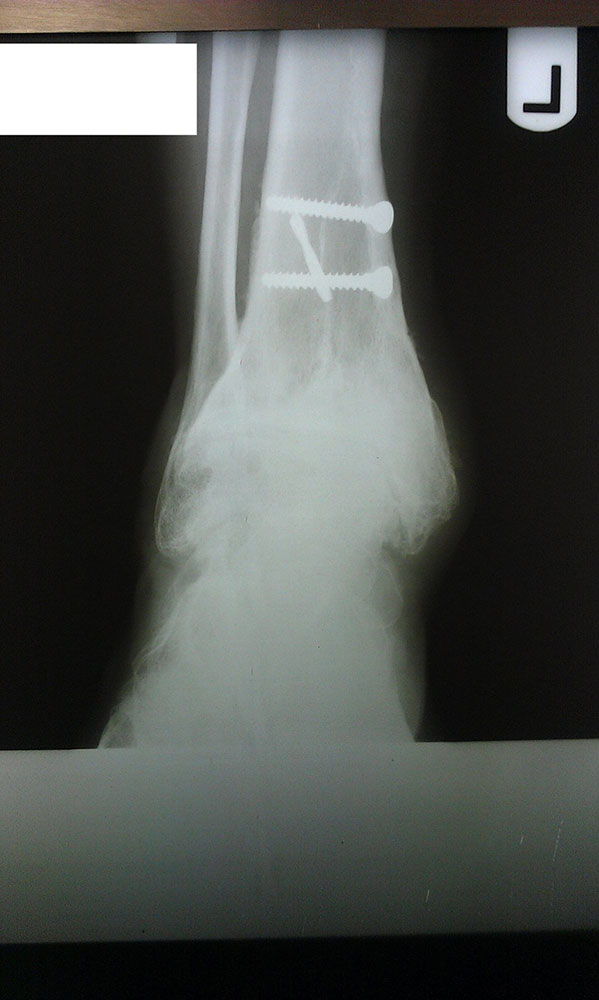

"Surgical misadventure" by another surgeon about 8 years ago. The wrong fixation was used for a flatfoot repair, & the deformity was not corrected. Patient came in with severe foot & ankle pain, with no arch at all. She was unable to play with her grandchild because the pain was so bad, & because she felt unsteady. The old hardware was removed, a lateral calcaneal lengthening osteotomy was performed along with a medial column/1st ray realignment. The ankle was painfully arthritic, & patient elected a total ankle replacement vs. an ankle fusion. She is now able to walk pain free & play with her grandchildren!